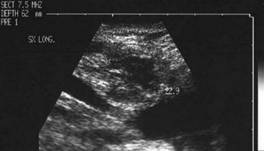

Femeie de 29 ani. Linfonodul in regiunea

laterocervicala dreapta ( 7x12x23mm, 1 cc) in neoplazie papilara a tiroidei. Structura

parenchimatoasa, neomogenea, cu margini

nete, cu absenta hilului.Examen citologic: metastaza de neoplazie papilara.

Lob drept,

proiectie trasversala si longitudinala

Aceeasi pacienta. Nodul de consistenta dura in lobul

drept spre istm.

Ecografia: nodul cu margini indistinte care deformeaza marginea anterioara a glandei,

parenchimatoasa, neomogena, hipoecogena. Prezenta de linfonodi laterocervicali.

Ctoaspiratie: carcinom papilar.